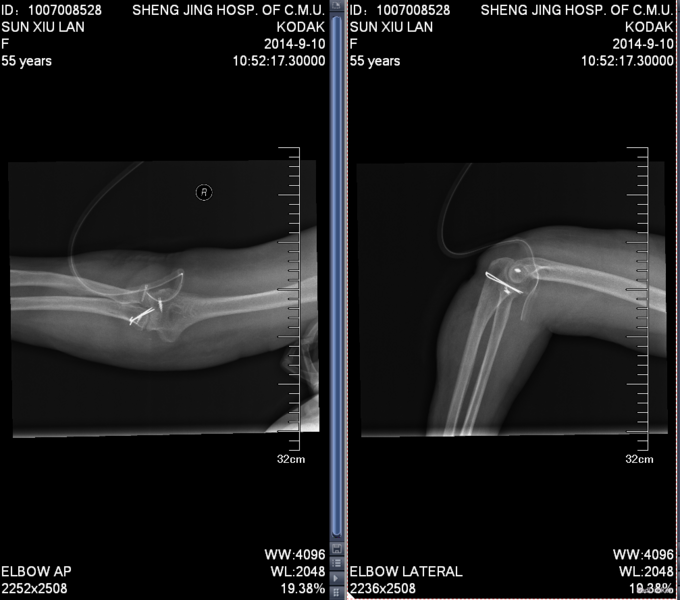

主诉:摔伤后右肘部疼痛10小时 患者自述2014-9-2 早8点自己走路时不小心摔倒,右肘部着地,导致右肘部疼痛、肿胀、活动受限,于当地医院拍片诊断为“右肘关节脱位”,给予手法复位, 为求进一步治疗来我院,诊断为“左肘关节骨折”,并收入我科,患者自受伤以来,无发热,无呼吸困难,无腹痛腹泻,饮食睡眠正常,大小便未见异常。

患者步入病房,左肘关节肿胀明显,压痛(+),骨擦音及骨擦感(+),左上肢感觉未见异常,左手指活动正常,左桡动脉搏动可触及。

患者入院后左肘关节石膏固定,左肘关节对症消肿等治疗。1周后完善检查后查无明显手术禁忌症后行左桡骨小头骨折切开复位内固定术。